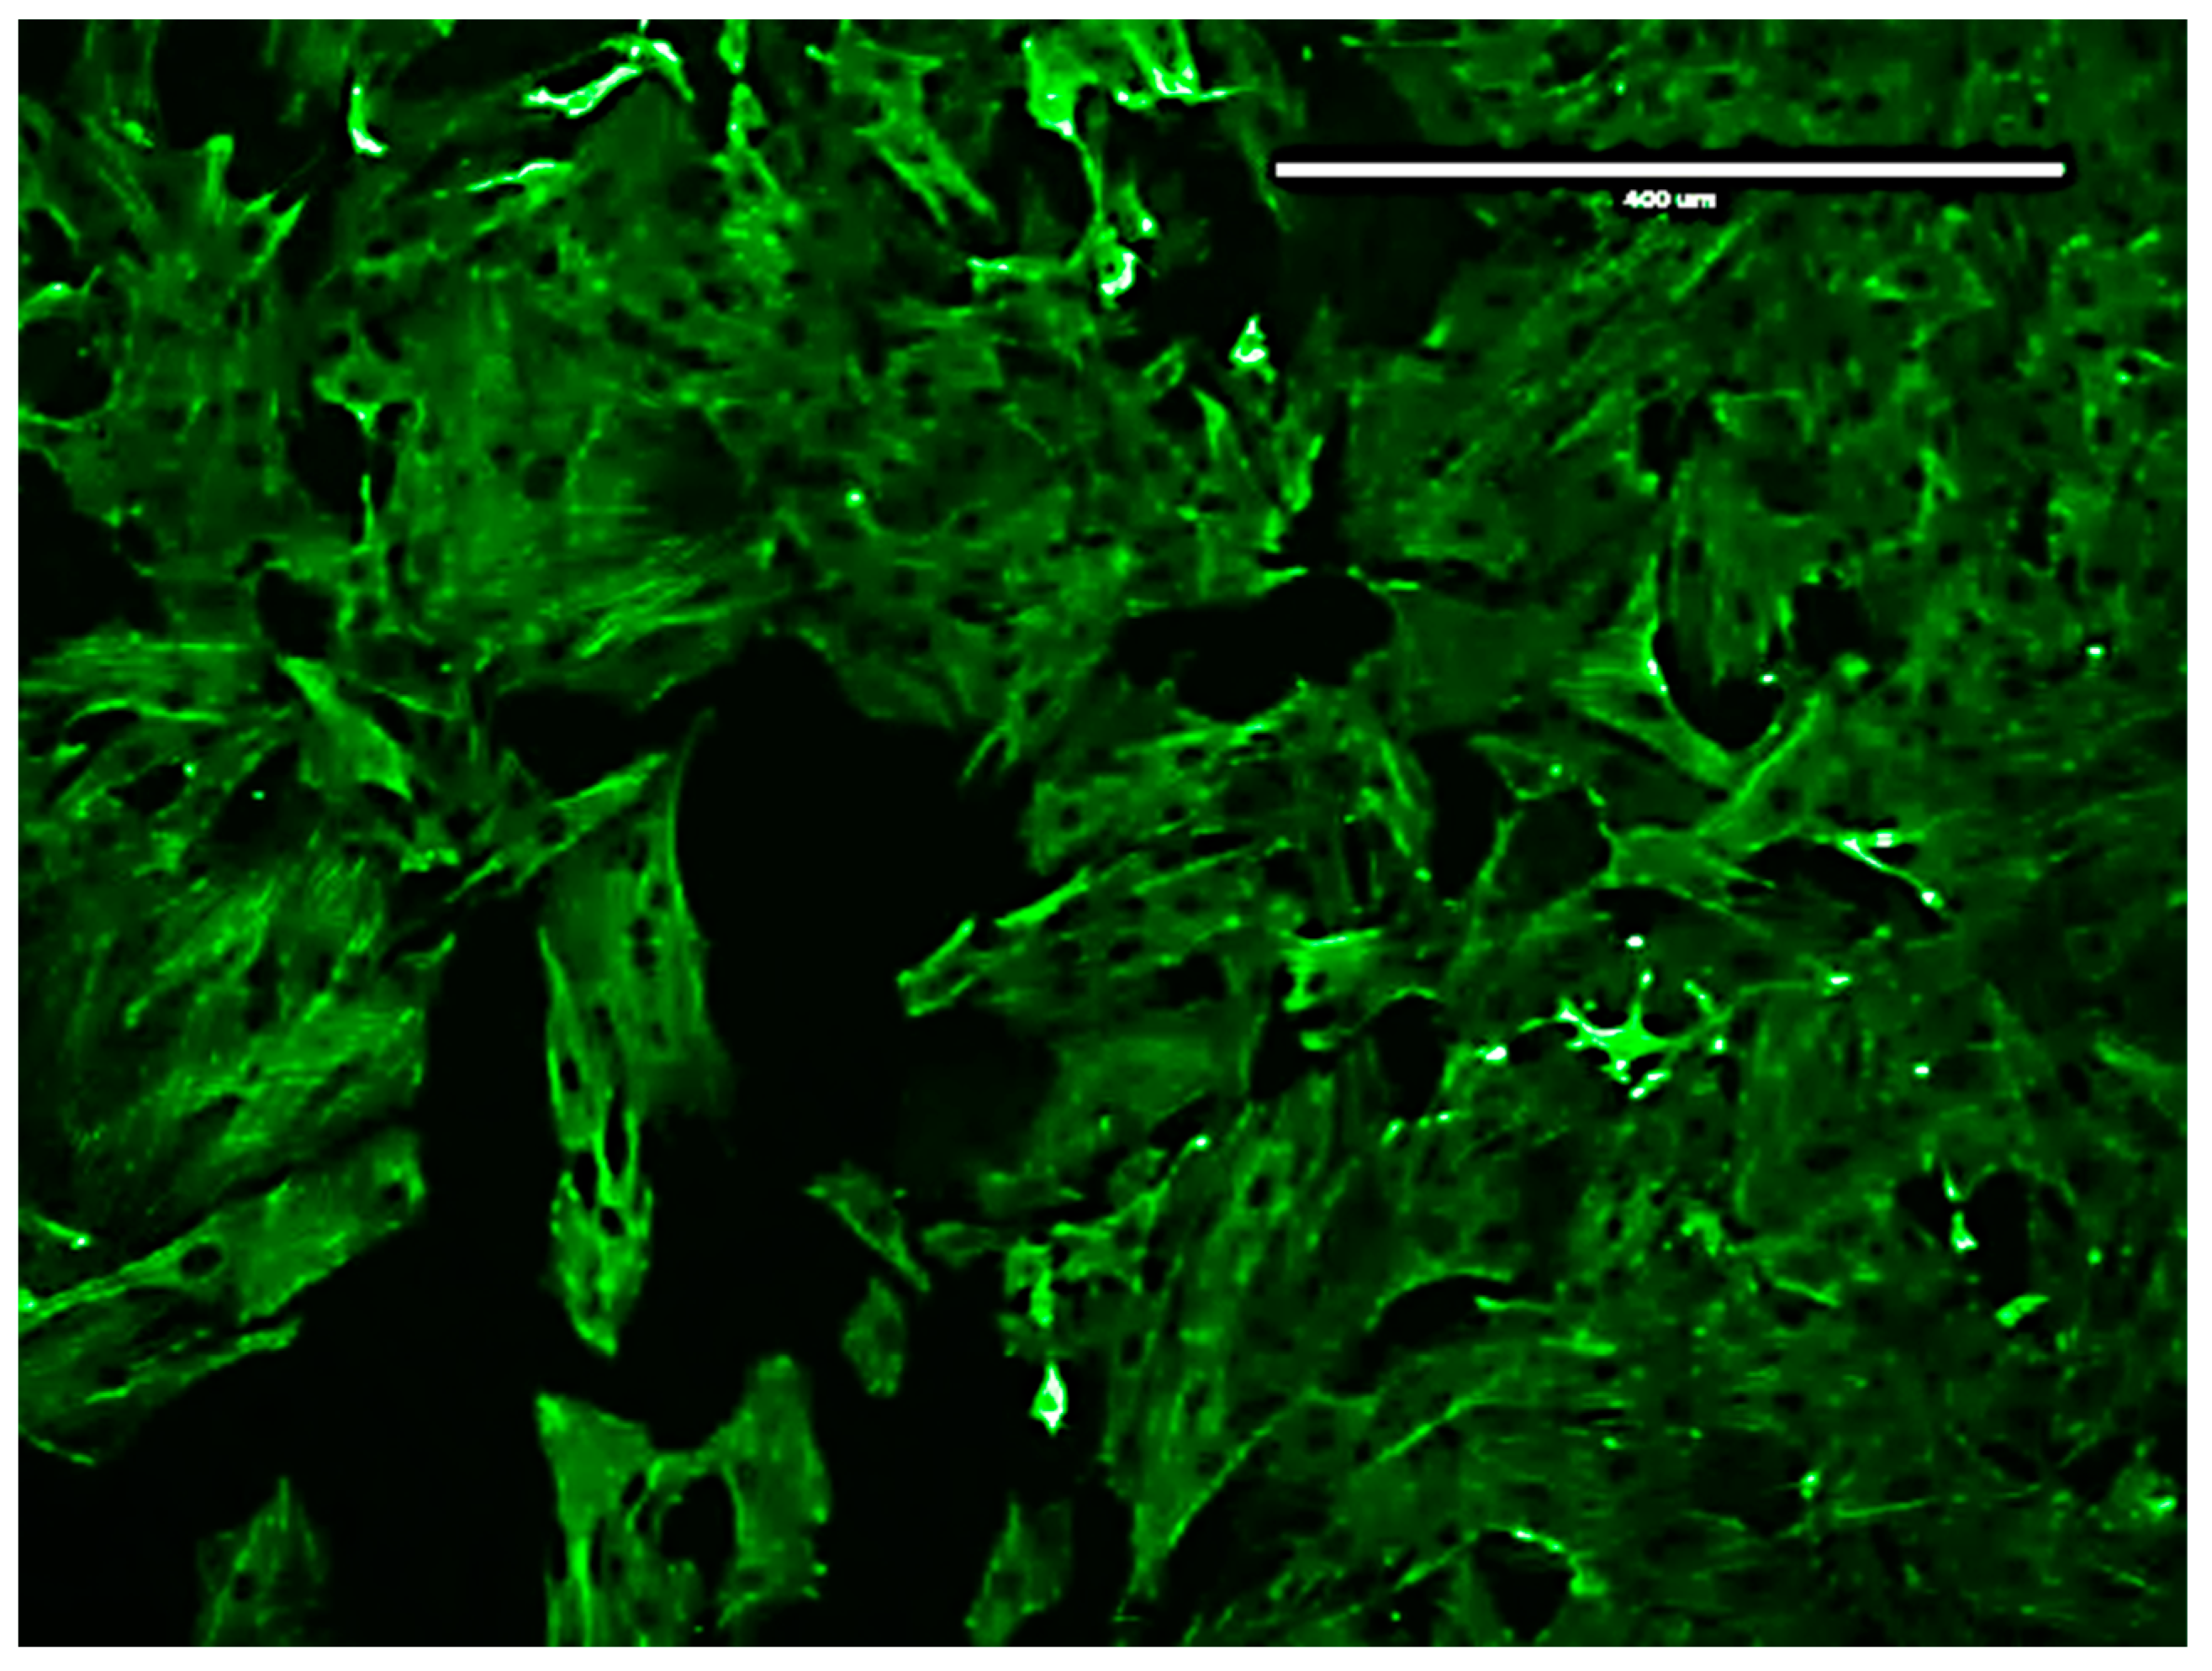

Figure A2 is a visual presentation of the stained rat aortic VSMCs depicting the presence of SM22α actin fibers.

Figure A2.

Immuno-stained microscopic image of rat aortic VSMCs depicting the presence of SM22α actin fibers (scale bar: 400 μm, magnification: × 10).